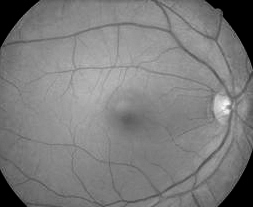

正常眼底

说到老年性黄斑变性先要了解黄斑是什么。它既不是绿色树叶生病而出现的黄色斑点,也不是人们脸上长出的那些令人不快的色斑。其实黄斑不是斑,它是我们眼睛看东西最关键的部位,是视网膜上是一个正常结构。如果把照相机比作眼睛,视网膜就是这个照相机的胶片,而黄斑就是视网膜胶片上最中心、最重要的部分。离开了这部分,无论你有再昂贵的相机,再好的镜头,都拍不出好的照片来。黄斑也像容颜一样会变老,在黄斑发生老化的时候,首先会长出一些类似老年斑样的东西,叫作玻璃膜疣。出现了这个玻璃膜疣,我们就称它为发生了干性老年性黄斑变性。而在一些特殊情况下,眼底黄斑区还会长出一些有问题的新生血管,这些新生血管会发生出血和渗漏,类似于水管发生漏水,所以又称之为为湿性老年性黄斑变性。视力因此也会经历由视物模糊、中心小暗点出现、直到中心巨大暗点出现的变化过程。